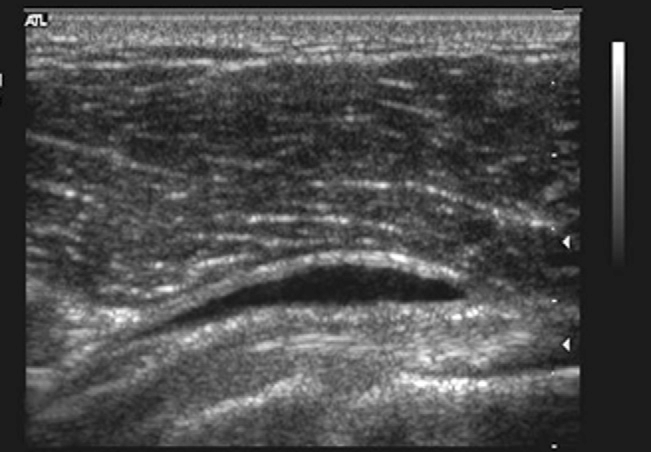

Ultrasound

Ultrasonography of the right shoulder showed subacromial subdeltoid bursitis demonstrated as a hypoechoic fluid collection superficial to the rotator cuff and deep to the deltoid muscle.

Ultrasound is another imaging modality that uses sound waves to generate real-time images of the internal structures of the body. In the case of subacromial bursitis, ultrasound is particularly valuable for its ability to assess dynamic movements and provide a real-time view of the shoulder.

Advantages of Ultrasound in Subacromial Bursitis

- Dynamic Assessment : Ultrasound allows for dynamic evaluation of the shoulder joint, making it possible to assess movement-related changes and impingement.

- Real-Time Guidance : Ultrasound is often used for image-guided procedures, including bursa injections, allowing for precise placement of the needle into the inflamed bursa.

- Cost-Effective : Compared to MRI, ultrasound is generally more cost-effective and readily available for point-of-care imaging.

Clinical Use

- Confirmation of Diagnosis : Both MRI and ultrasound can help confirm the diagnosis of subacromial bursitis by visualizing signs of inflammation, such as fluid accumulation within the bursa.

- Differential Diagnosis : These imaging studies aid in ruling out other shoulder pathologies that may present with similar symptoms.

- Treatment Planning : Imaging findings guide healthcare professionals in developing an appropriate treatment plan, whether it involves conservative measures, physical therapy, or interventional procedures like bursa injections.